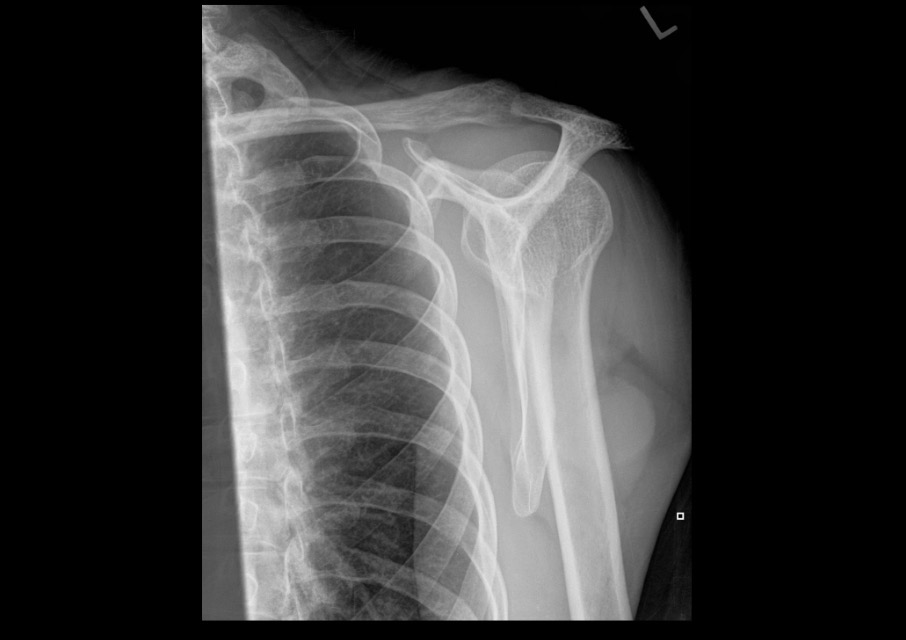

What projection position is this image?

AP Shoulder with Internal Rotation Left